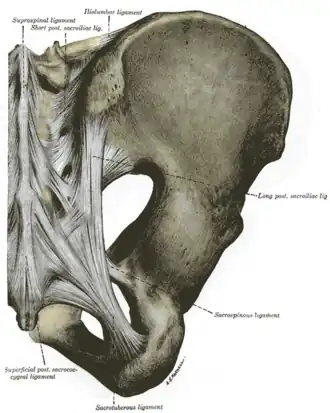

Le ligament sacro-tubéral est une large bande fibreuse.

Il s'insère en dedans sur l'épine iliaque postérieure et inférieure, sur l'épine iliaque postérieure et supérieure, sur les parties adjacentes de la fosse iliaque interne adjacentes aux épines iliaques, sur le bord latéral du sacrum et des premières vertèbres coccygiennes.

Les faisceaux convergent en bas, en avant et en dehors vers une partie rétrécie avant de diverger, ce qui donne au ligament un aspect torsadé.

Il se termine en dehors sur le bord médial de la tubérosité ischiatique.

Certaines fibres se prolongent vers la branche de l'ischion pour former le processus falciforme du ligament sacro-tubéral (ou prolongement falciforme du grand ligament sacro-sciatique ou repli falciforme du grand ligament sacro-sciatique). Il contribue au canal pudendal.

Quelques fibres se prolongent avec le tendon du long chef du muscle biceps fémoral.

Sa face antérieure entrecroise la face postérieure du ligament sacro-épineux.

Le ligament sacro-tubéral contribue à la consolidation de l'articulation sacro-iliaque.

Ce ligament ferme en arrière et en bas les petite et grandes incisures ischiatiques qu'il transforme avec la contribution du ligament sacro-épineux en petit foramen ischiatique et grand foramen ischiatique.